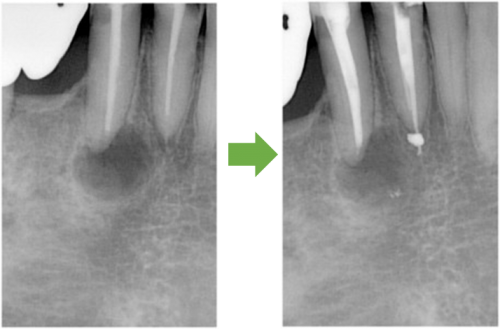

根の先に病巣ができています。

かぶせ物と土台を外します→根の管に詰まっている薬を外します→再び根の管を拡げます

根の管を拡げ終えました→症状がなくなりました→最終的なお薬を詰めます